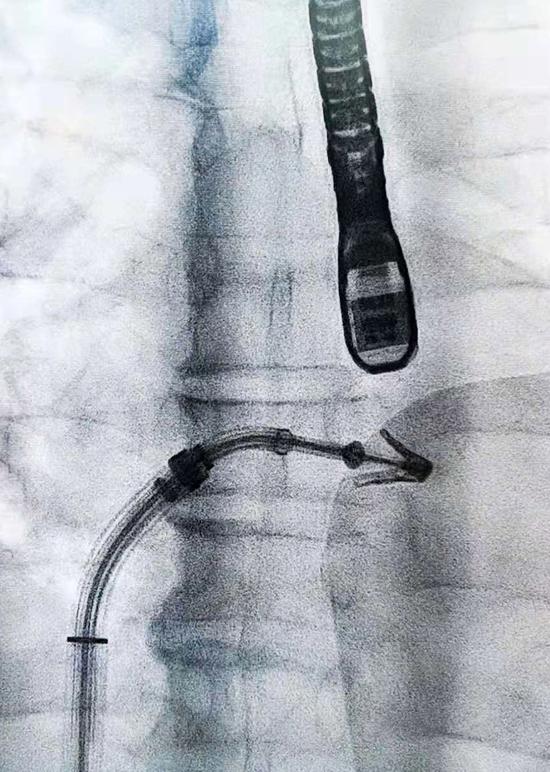

4月10日上午,何大爷的手术在厦心杂交手术室进行。手术全程都在跳动的心脏上完成,厦心院长王焱教授率团队将一个特制的夹合器经股静脉送入、穿刺房间隔、进入左心房,在食道超声及 X 线引导下,使用夹合器夹住二尖瓣前、后瓣返流严重部位,如同订书机装订一般,使二尖瓣在收缩期由大的单孔变成小的双孔,缩小瓣口面积,从而减少二尖瓣返流,让二尖瓣恢复正确的打开和关闭效果。这一超微创手术持续了3个多小时,术后超声评估显示患者二尖瓣返流基本消失。这也是我省开展的第一例经导管二尖瓣钳夹术。

微创经股静脉送入夹合器

特制的二尖瓣夹合器